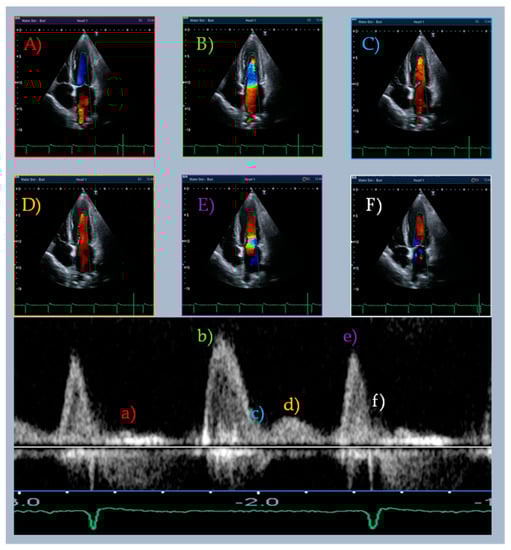

| Doppler-Parameters | Values | Chambers | Values | Strain and Strain Rate Parameters of LV and LA | Values | Time to Peak (ms) | %RR |

|---|---|---|---|---|---|---|---|

| E wave (cm/s) | 119.8 | IVS (mm) | 11 | GLS (%) | −16.7 | E wave | 49 |

| L wave (cm/s) | 32.3 | EDD (mm) | 53 | SR-irt (1/s) | 0.06 | G–E’ | 53 |

| A wave (cm/s) | 100.6 | EDV (mL/m2) | 63.9 | SR-E (1/s) | 0.69 | SR-E | 56 |

| E/A ratio | 1.2 | ESV (mL/m2) | 23.3 | E/SR-ivrt ratio (cm) | 1997 | G–L’ | 73 |

| E’ lat wave (cm/s) | 8.2 | LVEF (%) | 63 | E/SR-E ratio (cm) | 1.7 | L wave | 73 |

| L’ lat wave (cm/s) | 3.0 | LAVi (mL/m2) | 42.2 | SR-L (1/s) | 0.13 | SR-L | 75 |

| A’ lat wave (cm/s) | 13.8 | G–L’ (cm/s) | 0.59 | ||||

| E’ ivs wave (cm/s) | 8.1 | LA strain reservoir (%) | 34.2 | ||||

| L’ ivs wave (cm/s) | 2.2 | LA strain conduit (%) | 13.6 | ||||

| A’ ivs wave (cm/s) | 5.8 | LA strain contraction (%) | 20.5 | ||||

| E/E’ | 14.7 | aSR-E (1/s) | −0.77 | ||||

| IVRT (PW) (ms) | 61 | aSR-A (1/s) | −1.39 | ||||

| DT (ms) | 178 | (E/E’)/LA strain reservoir | 0.44 | ||||

| S/D wave ratio | <1 | ||||||

| TRV (m/s) | 2.8 |